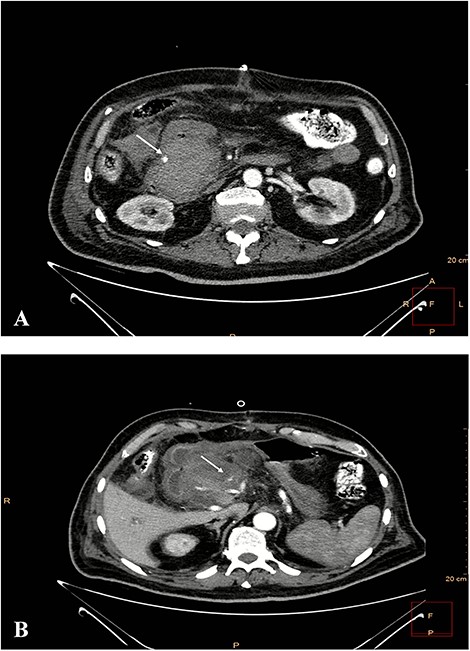

After the negative GI endoscopy for active bleeding, contrast-enhanced CT in the arterial phase was performed and revealed a pseudoaneurysm of the gastroduodenal artery with a diameter of 9 mm, and a second smaller pseudoaneurysm of a branch of gastroduodenal artery were demonstrating (Fig. 4). Furthermore, celiac-mesenteric trunk and worsening image of pancreatitis were depicted (Fig. 5). After that, emergency embolization of the pseudoaneurysms was performed, using a 4-F arterial sheath via the Seldinger technique. A celiac angiogram was obtained with a 4-F angiographic catheter type Cobra (Medical Materials, Boynton Beach, Florida, USA). Using microcatheter Asahi Caravel (Asahi-Intecc USA Medical, Tustin, California, USA), microcatheter SwiftNinja (Merit Medical, South Jordan, Utah, USA) and microcoils of (Boston Scientific, Marlborough, Massachusetts, USA) 2.5 and 3 mm, complete embolization of the two pseudoaneurysms was achieved (Fig. 6).

Contrast-enhanced CT in arterial phase. A pseudoaneurysm of gastroduodenal artery with a diameter of 9 mm (white arrow). B. Smaller pseudoaneurysm of a branch of gastroduodenal artery (white arrow).